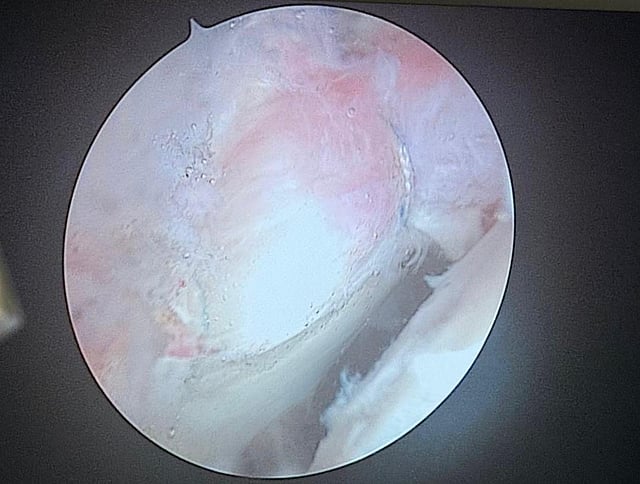

وأفاد تجمع المدينة المنورة الصحي بأن المستفيدة حضرت إلى العيادات وهي تعاني من آلام مزمنة في مفصل الورك مع صعوبة في الحركة نتيجة تمزّق في الغضروف الحُقّي (Labrum)، وبعد استكمال الفحوصات السريرية والتصويرية، تقرّر إجراء العملية بالمنظار كخيار متقدّم يوفّر دقة أعلى وأضراراً أقل على الأنسجة مقارنة بالجراحات التقليدية.

وأردف التجمع أن العملية أُجريت من خلال فتحات صغيرة، تم عبرها الوصول للمفصل وإصلاح التمزّق باستخدام تقنيات خياطة متقدمة تُحافظ على الغضروف وتعيد وظائف المفصل الطبيعية، حتى تكللت الجراحة بالنجاح دون أي مضاعفات، وتمكّنت المستفيدة من البدء في برنامج التأهيل الحركي خلال الساعات الأولى بعد العملية.